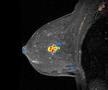

Confirma has spent years developing the extensive CAD algorithms, intellectual property and validation required of these highly technical clinical tools. The flagship product, CADstream, has over 1,200 systems implemented for breast and prostate MRI, and several additional solutions are in development. “Our customers understand the core benefits of CAD as a clinical workflow tool,” says Wayne Wager, CEO of Confirma. “By combining our patented CAD applications with Merge’s broader health IT solutions and global presence, we can better take advantage of current and future growth opportunities and, thus, extend our solutions to more clinicians.”